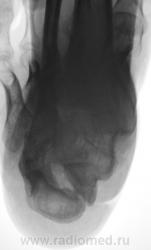

Лечение состояло из "множества рентгенов" и гипса. Срок - 5 месяцев.

Сейчас думают об остеомиелите.

Контуры пяточной кости относительно четкие, разрежение структуры пяточного бугра, в проекции перелома уплотнение структуры кости( имею в виду последние снимки).Клиника остеомиелита есть?

Клиники остеомиелита, с моей точки зрения, нет.

А что Вы в протоколе написали?Я тоже не вижу остеомиелита.

Во-первых, деформация пяточной кости; во-вторых, отсутствие консолидации, через некоторое время и ложный сустав сформируется. Неоднородное уплотнение костной структуры в теле кости может быть обусловдено как остеомиелитом, так и перераспределением нагрузки.

Признаков остеомиелита не вижу, только консолидир перелом с неуд стоянием отломков.